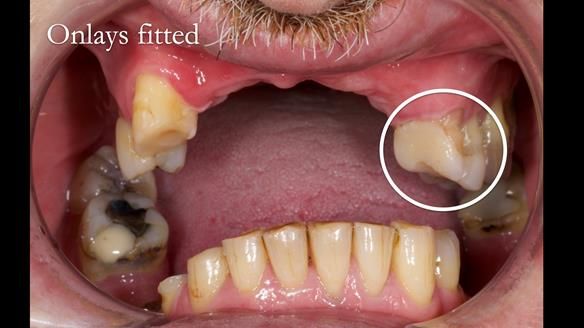

2. Onlay preparations: Composite onlays were fitted for his upper left premolars to repair these teeth and support the new denture.